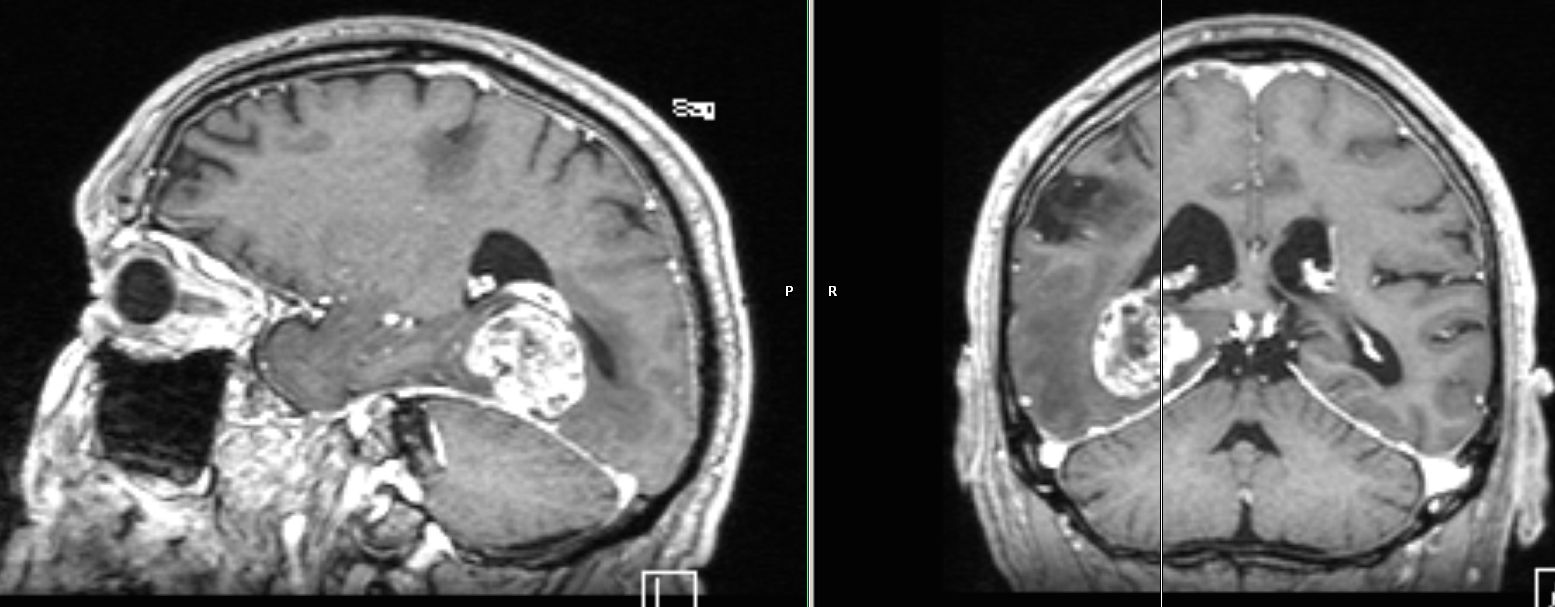

| zentrale Metastasen | 60-jähriger Mann, den vor einem Jahr ein

Plattenepithelkarzinom des linken Unterlappend cT2 pN2 Mo hatte. Nach 4x

Cisplatin-Vinorelbin und Bestrahlung vor 2 Monaten CR. Sturzes in der

Häuslichkeit eingewiesen werden. Jetzt Schwindel und zunehmende

Gangunsicherheit.

![]() |